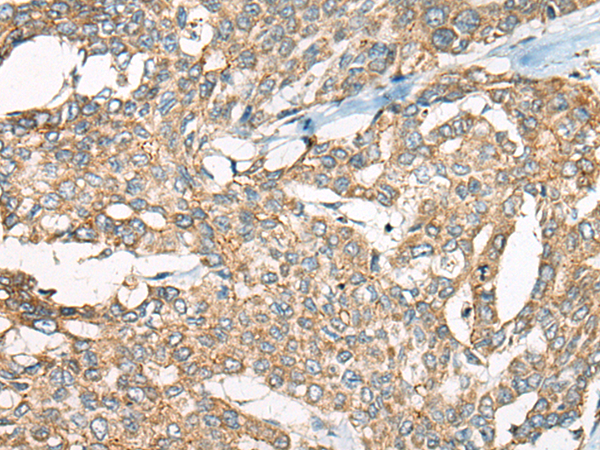

分类: 科研抗体货号: P12832别名: ZNF913; ZNF-U69274应用: IHC反应种属: Human